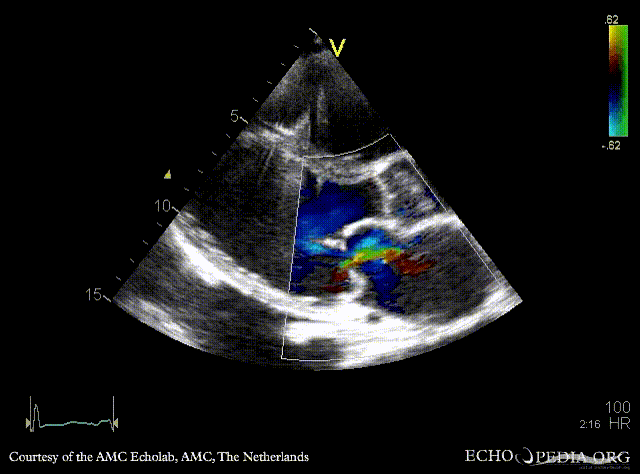

E00454.gif E00455.gif

A4CH: prolaps of PMVL, enlarged left and right atrium, poor function of dilated right ventricle A4CH: Color doppler, severe mitral regurgitation